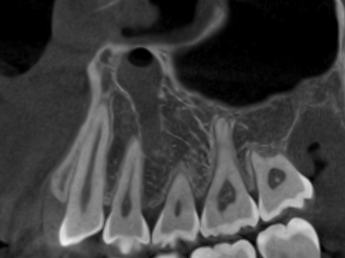

(兩條紅線中間黑色區域即為神經管)